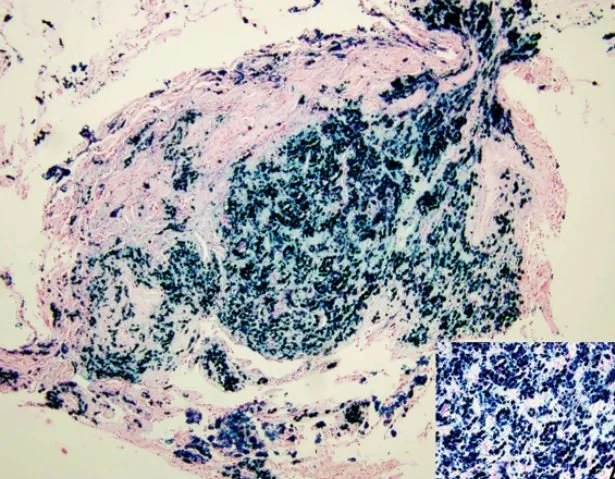

Pulmonary siderosis- is caused by chronic inhalation of iron oxide fumes during welding with iron accumulating in the lungs. Small nodules are seen in the lungs on cxr and chronic lung which can be asymptomatic.

iron in the lung of a welder stained with Prussian blue.